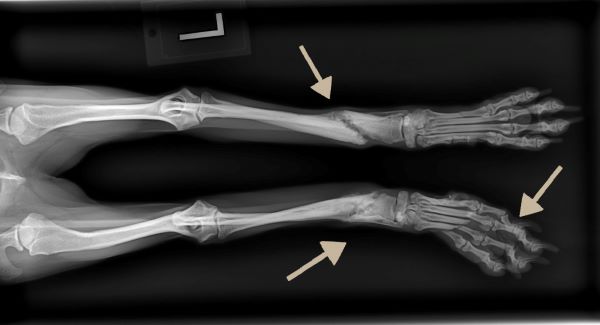

Our veterinary team quickly treated her pain and performed x-rays to assess the severity of her injuries. Two bones are broken in each of Daphne’s two front legs, and she has 5 broken toes.

Daphne sits like a baby kangaroo to keep pressure off her front toes. Her fractures are in different stages of healing indicating that the injuries occurred at different times. This suggests that poor Daphne may have been intentionally harmed more than once in her short life.

At just 9 pounds, Daphne needs splints to stabilize her small broken toes, and she will be on strict crate rest to give her time to heal.